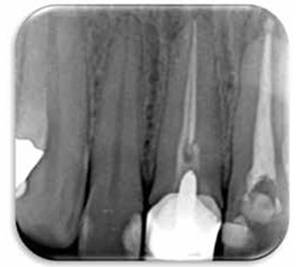

Paciente masculino de 36 años de edad sin antecedentes patológicos personales (A.P.P.) se presenta al Postgrado de Endodoncia de la Universidad Latina de Costa Rica por motivo de Trauma Dental debido un accidente laboral, el hecho ocurrió tres días anterior a su visita al centro de atención. Clínicamente se observa inflamación y un grado de movilidad II. Desalojo incisal y fuera de oclusión. (Figur 3) Radiográficamente se observa una obturación deficiente del conducto y a la vez una aparente fractura radicular. (Figura 4)

Figura 4: Radiografía inicial